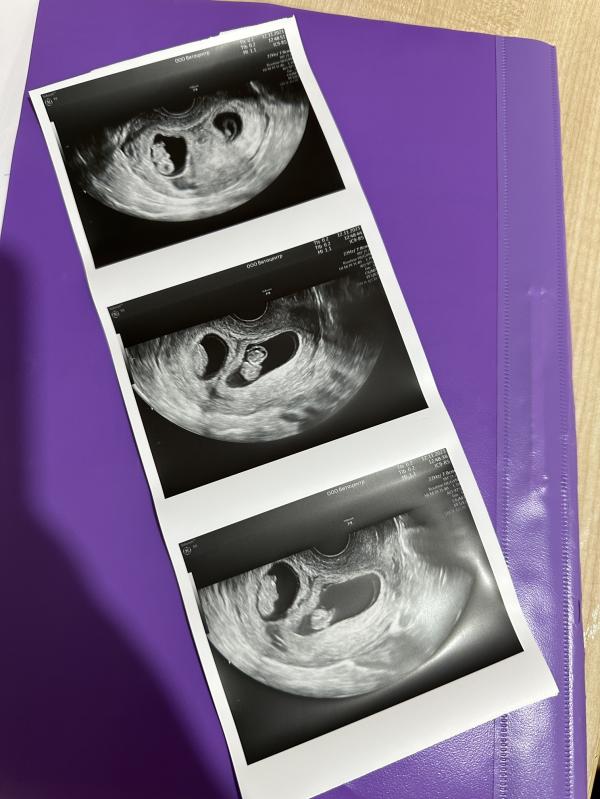

Сегодня было первое УЗИ 😇

Первыми словами ждала «у вас все хорошо», а меня огорошили «у вас двойня».

Теперь привыкаю к мысли, что будет два малыша 👶🏼👶🏼